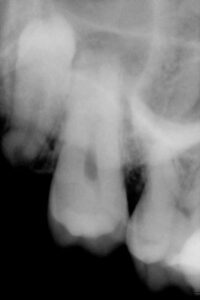

Infections and/or periodontal disease

Cavities that cannot be restored

Damage to neighboring teeth